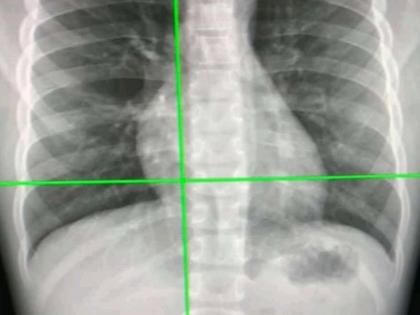

Tokyo, Aug 18 Japanese scientists have developed an advanced artificial intelligence (AI) model that utilises chest radiographs to accurately estimate a patient's chronological age.

In the case of a disparity, the AI model can signal a correlation with chronic disease. These findings, published in The Lancet Healthy Longevity, mark a leap in medical imaging, paving the way for improved early disease detection and intervention.

The team from Osaka Metropolitan University first constructed a deep learning-based AI model to estimate age from chest radiographs of healthy individuals. They then applied the model to radiographs of patients with known diseases to analyse the relationship between AI-estimated age and each disease.